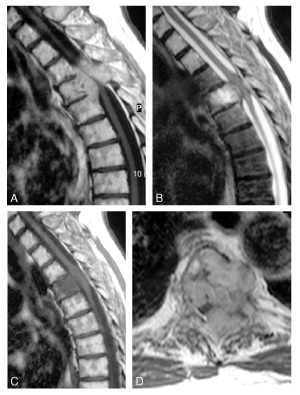

Quel diagnostic?

myélopathie cervicarthrosique C4-C5 avec hypersignal médullaire

Diagnostic?

Neurinome en sablier T5 -T6 gauche

(dans l’ordre de gauche à droite et de haut en bas: abcd)

Quel diagnostic pour chaque photo?

a =hématome extradural

b=hématome sous dural

c=contusions cérébrales

d= tumeur cérébrale